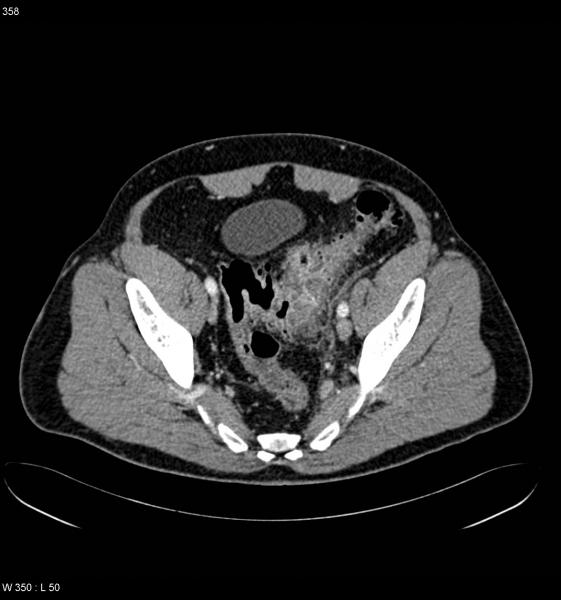

Isquemia mesentérica: Aguda y crónica